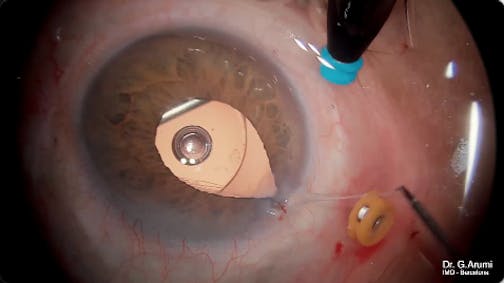

Myopic Macular Hole

Jose Garcia Arumi, MD